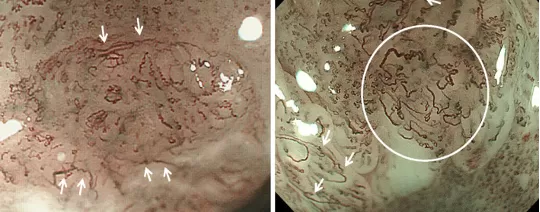

Ở đại trực tràng, kỹ thuật nội soi phóng đại kết hợp tăng cường hình ảnh đặc biệt hữu ích trong việc phát hiện các polyp nhỏ hoặc tổn thương phẳng – những dạng tổn thương dễ bị bỏ sót khi chỉ sử dụng nội soi thông thường. Ngoài ra, phương pháp này còn giúp nhận diện các đặc điểm gợi ý ác tính, hỗ trợ bác sĩ lựa chọn chiến lược xử trí phù hợp nhất cho người bệnh.

Hình ảnh: nội soi phóng đại polyp đại tràng